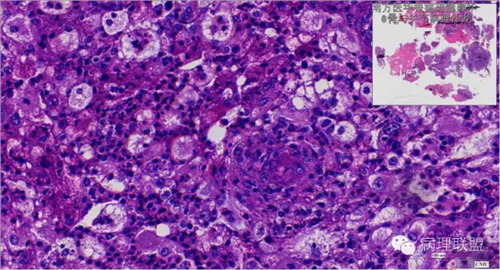

来源于组织细胞的相似性骨病ECD vs RDD 看图说话